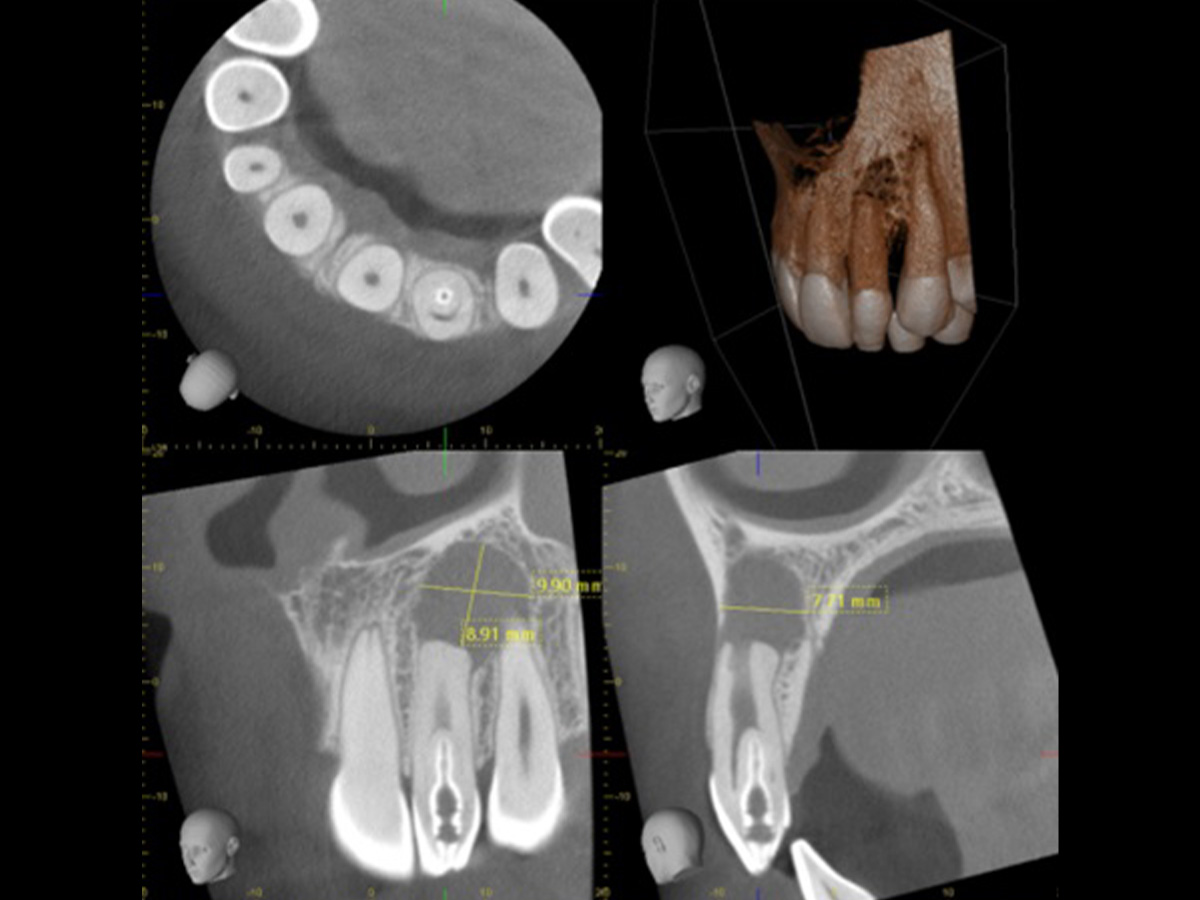

Modul I. Digitale endodontische Diagnostik

Viele Zahnärzte nutzen die Digitale Volumentomografie (DVT) im Alltag nicht, da ihnen die grundlegenden Kenntnisse über diese Technik fehlen. An den Universitäten werden die endodontischen Konzepte häufig nur anhand von Einzelbildern vermittelt, weshalb in der Praxis das notwendige Wissen fehlt, um diese Technologie sinnvoll am Patienten einzusetzen. Erlernen Sie in praktischen Übungen am Computer, wie die DigitaleVolumentomografie (DVT) die endodontische Diagnostik und Behandlung beeinflusst. „Der Behandlungsplan ändert sich in etwa 50 % der Fälle, nachdem der Behandler eine DVT beurteilt hat“ (Rodriguez et al., Journal of Endodontics, 2015: Influence of Cone-beam Computed Tomography on Endodontic Retreatment Strategies among General Practitioners and Endodontists).Aus diesem Grund gewinnt diese Technik zunehmend an Bedeutung. Erfahren Sie mehr über die Vorteile dieser diagnostischen Methode, ihre Indikationen und Anwendungen. Unterstützt von der Carestream CS 3D Imaging Software analysieren Sie Schritt für Schritt verschiedene Fälle und erstellen eine präzise Diagnose sowie eine fundierte Therapieplanung.